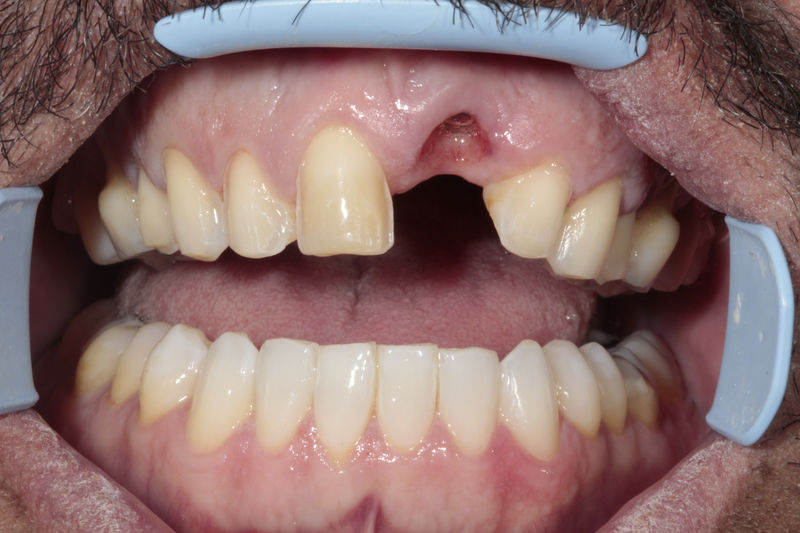

Implante fracasado, extracción, carillas, coronas y prótesis fija.

Los implantes dentales son pequeños tornillos de titanio u otro material biocompatible que se insertan en el hueso maxilar o mandibular para sustituir la raíz de un diente perdido. Actuando como un soporte sólido sobre el cual el dentista puede colocar un diente artificial (corona), un puente o una prótesis completa.

Son estructuras de titanio las cuales se colocan en el hueso y se utilizan para soportar coronas, prótesis fijas, removibles y totales. La colocación de los implantes se hacen previo análisis tomográfico.